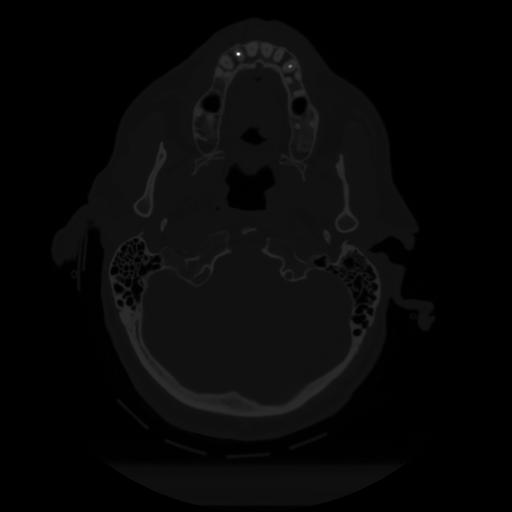

12 P.BLANDAS,,Vol,0.5,P.BLANDAS,,